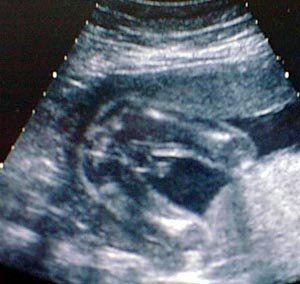

الأسبوع ال17

الأسبوع ال18